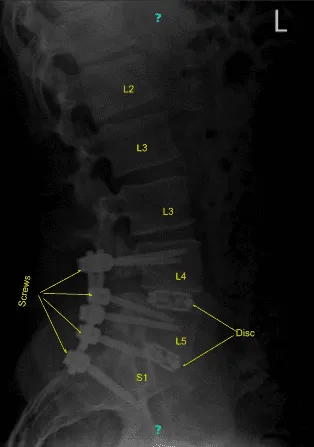

Aero was brought in and a spin was done to obtain CT scan images. The navigation reference was verified. Having navigation ready, pedicle screws were planned to be inserted first on the left L4 followed by right L4, left L5, right L5, left S1, and right S1 sequentially.

All the entry points were marked with the reference probe followed by drill, followed by navigator gear shift, navigator tip and insertion of pedicle screws on bilateral L4, bilateral L5, and bilateral S1.

The end space was prepared again and a 36 mm x 10 degree expandable Globus cage was inserted. It was medialized. Pictures on fluoroscopy were taken and found to be acceptable but it felt that the cage on the L4-L5 was a little lateral, so it was removed and reinserted more medially and found to be in satisfactory position this time.

After that, a low dose CT scan with Aero was again done to confirm the placement of the screws and the cage. The newly taken pictures showed satisfactory positions of all the six pedicle screws and the cages x 2. Further adhesions of both bilateral L4,bilateral L5, and bilateral S1 nerve roots were released with the use of Penfield and Woodson tool.

Final pictures were taken and saved. The neuromonitoring was stable during the time. Closure was done with insertion of drains. Patient was flipped supine and moved to recovery in a stable condition.